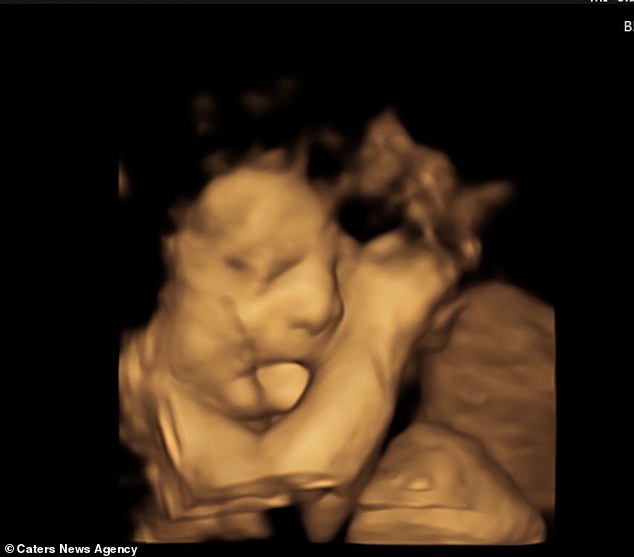

帶大家來看美國的一位新手媽媽,她在懷孕27週時和先生去醫院照超音波,進行產檢,當天在超音波影像中,這位媽媽和先生看到肚中的寶寶不斷吐舌頭,他們當下以為寶寶是在賣萌,無意間對爸比媽咪展露可愛的一面。

看到小孩在腹中可愛的模樣,想說能否麻煩醫生截取超音波影像,把照片傳給親友分享。但後來發現事情並沒有想像中單純,醫生認為寶寶一直吐舌頭不太對勁,提議夫妻倆能否馬上進行剖腹產。

孩子的爸媽聽到當然緊張壞了,趕緊剖腹看看寶寶,當寶寶順利生下時,一看見他的全臉,媽媽這才驚覺,原來寶寶當時在肚子裡並不是在吐舌賣萌,而是因為罹患了罕見疾病。

寶寶罹患一種叫Beckwith-Wiedemann Syndrome簡稱BWS,是一種先天性過度生長的疾病,進而造成舌頭異常腫大的現象。經醫生檢查才得知,寶寶的舌頭因為是普通的兩倍大,所以才會吐露在口腔外。